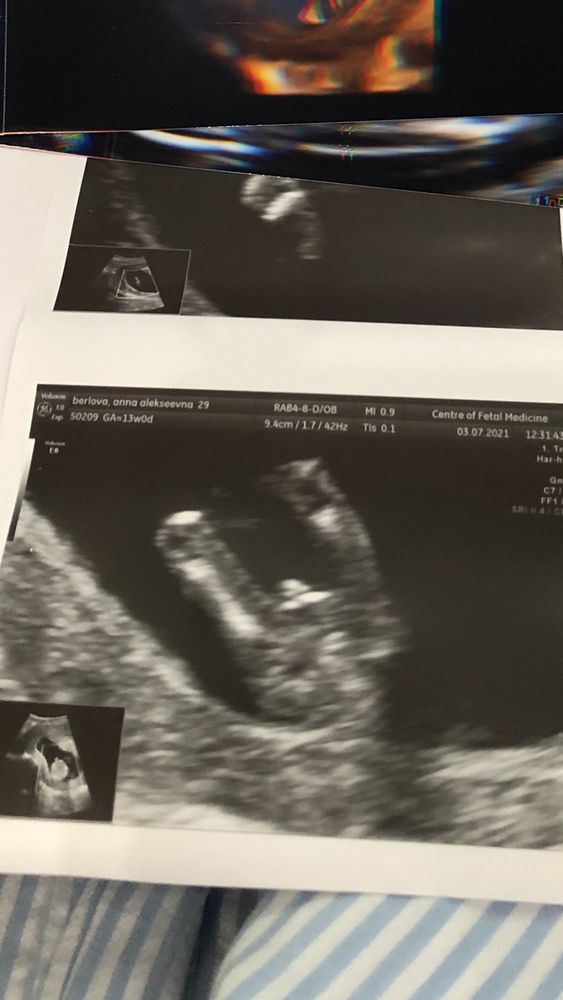

Первый скрининг

Сегодня сходили. По узи все отлично.

Лежит там такой гражданин) или гражданка))) док сказала, похоже на пацана, но не точно. Говорит, надейтесь, может и девочка. А мы тааак девочку хотим))) сб 160